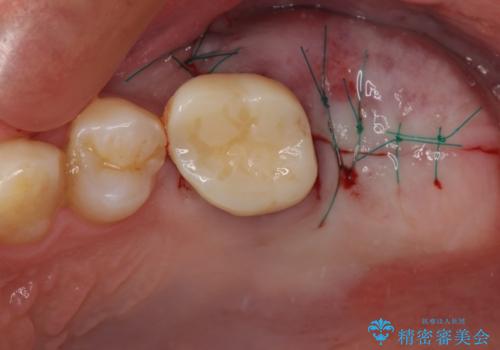

手前の歯は状態は良くないものの、抜歯するほどではないと判断したため、根管治療後にオールセラミッククラウンにて補綴治療を行うこととしました。

術後半年でレントゲン写真を撮影したところ、インプラント周りの骨は安定しており、根管治療を行った歯周辺の病変はきれいに改善されていました。